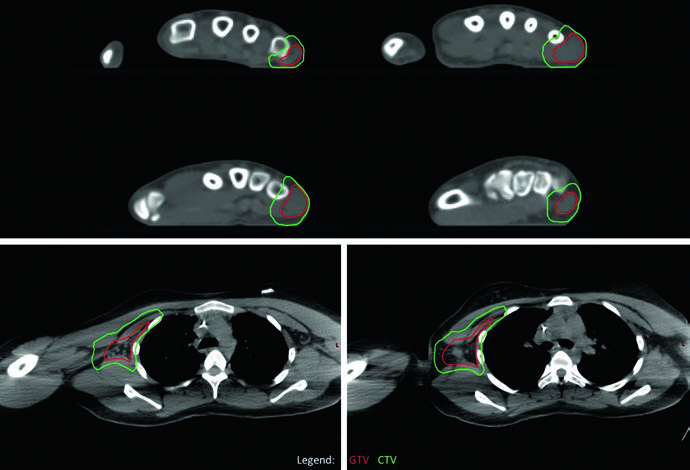

Um ponto prático central é o manejo do GTV1 quando o tumor se estende para cavidades corporais. Se a imagem pré-tratamento mostra tumor “empurrando” pulmão ou vísceras pélvicas — sem invasão direta — o GTV1 pode ser adaptado após a quimioterapia de indução para refletir a regressão tumoral nesses espaços. Essa adaptação aparece claramente no caso de EWS pélvico, onde o nível inferior não apresenta doença residual (GTV2) e a extensão do GTV1 para a pelve foi reduzida para compensar a resposta à quimioterapia. O PTV1 recebeu 45 Gy e o PTV2 recebeu 10,8 Gy adicionais, totalizando 55,8 Gy.

No caso de EWS de parede torácica, a simulação com TC de quatro dimensões (4DCT) foi realizada para capturar a excursão respiratória completa dos volumes-alvo. O tumor original ocupava a metade posterior do hemitórax esquerdo, mas o GTV1 foi adaptado para refletir o “pushing” tumoral no espaço agora ocupado por pulmão normal. A cobertura dos sítios de contato e envolvimento originais foi mantida. Da mesma forma, PTV1 recebeu 45 Gy e PTV2 um boost adicional de 10,8 Gy.

O delineamento de volumes no RMS segue princípios semelhantes aos do EWS, mas com particularidades para tumores parameníngeos e lesões que “empurram” estruturas adjacentes.